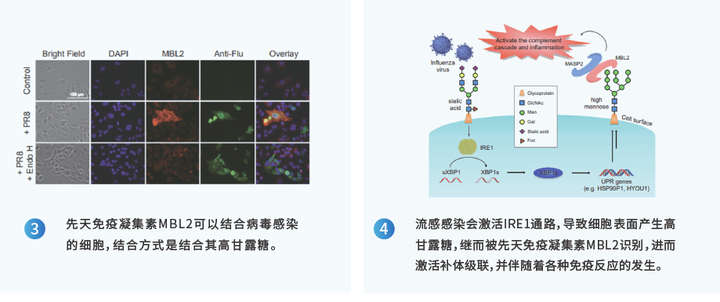

经典案例1:凝集素芯片发现与流感病毒感染相关的宿主糖蛋白